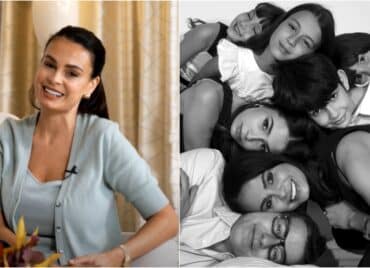

Corina a născut două fetițe gemene univiteline, obținute prin FIV, după mai bine de un deceniu de încercări nereușite. Povestea unei mame extraordinare și a unor inimioare în oglindă. Reușită medicală în cadrul Centrului de fertilitate și FIV Regina Maria din Cluj. Prin fertilizarea in vitro, Corinei Tamaș i-a fost transferat un singur embrion, însă acesta s-a divizat în două. Fericita mămică își strânge astăzi la piept cele două fetițe minunate, care nu și-au luat prin surprindere doar părinții, ci și pe medici.

Corina a născut două fetițe gemene univiteline, obținute prin FIV. „Mamele fac medicina să fie extraordinară”, campania de recunoaștere a superputerii mamelor din România

Corina este una dintre mamele care fac medicina să fie extraordinară. Și-a urmat instinctul, a cercetat și a făcut cea mai bună alegerea pentru familia ei

Corina Tamaș: „Datorită echipei de medici de la Regina Maria am reușit să ne vedem visul împlinit și anume, să aduc pe lume două fetițe perfect sănătoase. Cu siguranță, faptul că am reușit să rămân însărcinată, am reușit să trec cu bine prin această sarcină și să aduc pe lume două fetițe minunate, mă fac să mă simt o femeie puternică, împlinită, fericită și încrezătoare în viitor.

Fetițele mele au venit pe lume după 23 de ani de conviețuit în doi, timp în care am încercat diferite tratamente. În momentul în care ne-am resemnat și am zis că nu vom avea copii niciodată, am fost îndrumați să apelăm la o procedură de fertilizare in vitro. Și am avut șansa ca după prima încercare să obținem fetițele, cele două minuni, pe care le consider cel mai mare câștig al nostru și ele ne luminează viața.”

Corina a născut două fetițe gemene univiteline, obținute prin FIV. Corina povestește că încercările nereușite de a rămâne însărcinată au fost cele mai grele momente din tot acest parcurs. Datorită sprijinului familiei și mai ales a soțului ei, Corina și-a găsit resursele de a merge mai departe, de a nu renunța la a încerca, de a-și urma visul de a deveni mamă. Cu răbdare, perseverență, încredere în echipa de medici, Corina și Silviu și-au împlinit cea mai mare dorință, aceea de a deveni părinți.